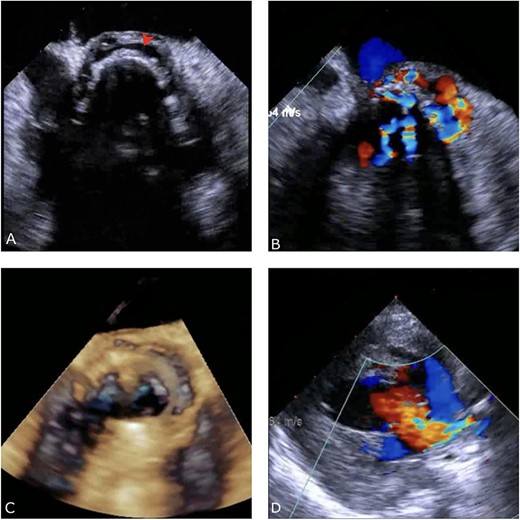

A thorough cardiovascular examination was performed, which revealed normal prosthetic valve clicks and a grade 3 ejection systolic murmur in the right second parasternal space. Further investigations included a transesophageal echocardiogram (TEE), which showed a paravalular anechoic free space around the prosthetic mechanical aortic valve with paravalular leakage and regurgitant flow with dehiscence of the prosthesis causing aortic stenosis (Fig. 1). A computed tomography (CT) scan was also performed to rule out aortic calcification, which revealed a normally seated aortic valve prosthesis with no visualization of the paravalular free space (Fig. 2). During the preoperative workup, blood cultures showed bacterial growth of Brucella melitensis. A multidisciplinary team approach was initiated, and the patient was started on antimicrobial therapy with gentamicin, doxycycline and rifampin. However, due to the patient developing abnormally high levels of Aspartate aminotransferase (AST) and Alanine aminotransferase (ALT), which is a side effect of rifampin, the regimen was changed to ceftriaxone, doxycycline and trimethoprim/sulfamethoxazole.

Preoperative CT demonstrating a previous aortic mechanical valve prosthesis.